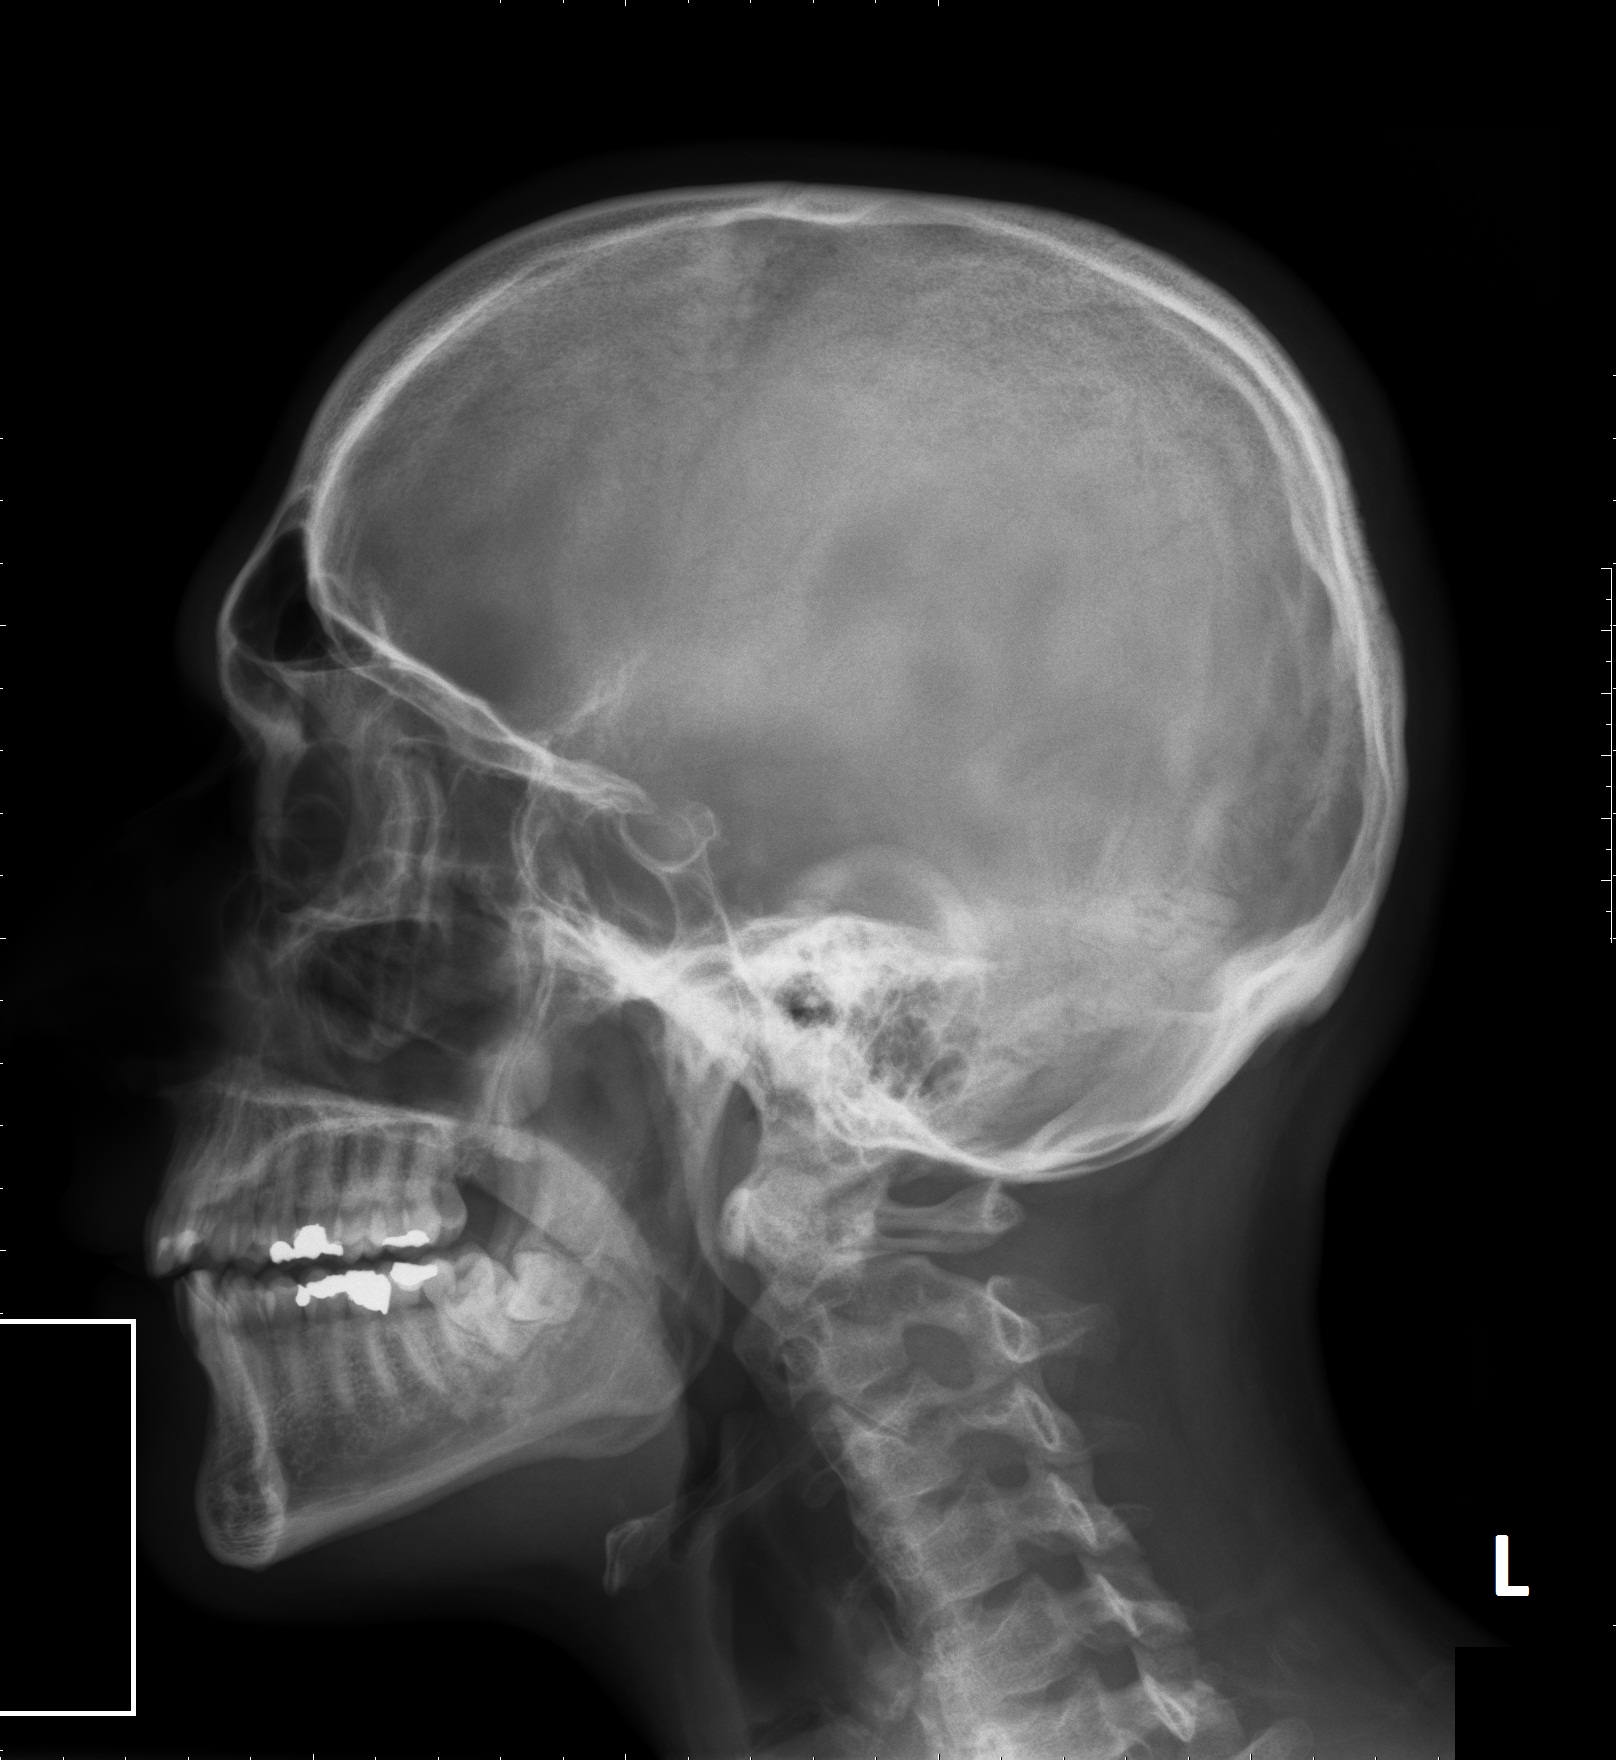

Badania ponad 1400 ludzkich czaszek (ludzi współczesnych żyjących w XX w. i reprezentujących różne grupy etniczne, a także skamieniałych czaszek sprzed ponad 80 tys. lat i w wieku od 10-38 tys. lat) przeprowadził Robert Cieri z University of Utah. Porównując łuki brwiowe, kształt twarzy i pojemność czaszek doszedł do wniosku, że z biegiem czasu ich budowa wyraźnie się zmieniała. Malał łuk brwiowy, a górna część twarzy stopniowo się skracała, dzięki czemu u naszych przodków stopniowo zanikły wydatne brwi, a kontur twarzy złagodniał.

Zmiany te odzwierciedlają coraz słabszy wpływ testosteronu na kościec – tłumaczy Cieri.